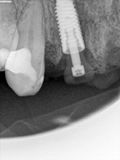

fredlibc | all galleries >> Galleries >> MTiu - immediate 12 and 21 > R3.jpg

R3.jpg